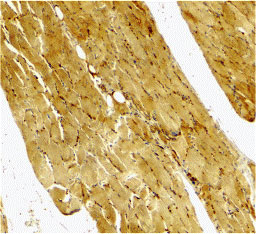

Immunohistochemical staining of human skeletal muscle using Caspase-7 antibody at 2 μg/mL. |